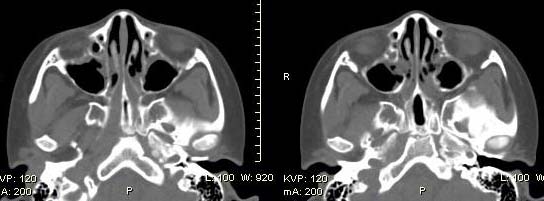

以下是引用随光逐影在2009-6-4 21:13:00的发言:[br]1)考虑鼻咽腺样体重度肥大。2)双侧鼻腔炎性改变。3)双侧上颌窦、双侧筛窦及左侧蝶窦炎症。

以下是引用zsl6918在2009-6-5 7:42:00的发言:[br]首先考虑鼻咽腺样体重度肥大,鉴别纤维血管瘤.强化有助明确.